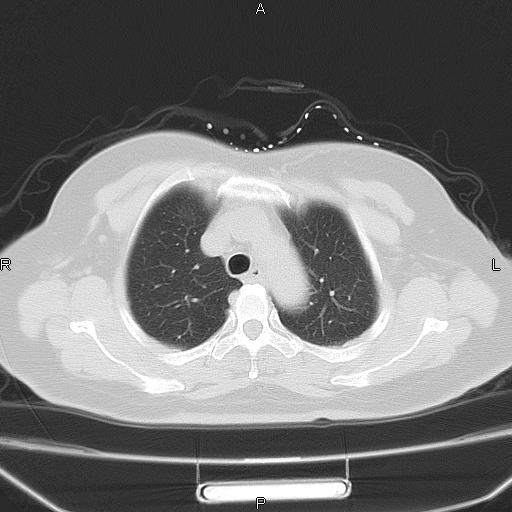

胸腺瘤

女、63Y 双眼睑下垂,早轻晚重。 胸腺瘤???

结果胸腺瘤